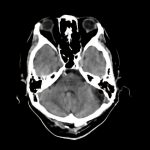

小脳テント髄膜腫

聴神経腫瘍

断層撮影

手術前1

No.’13_150 手術前1